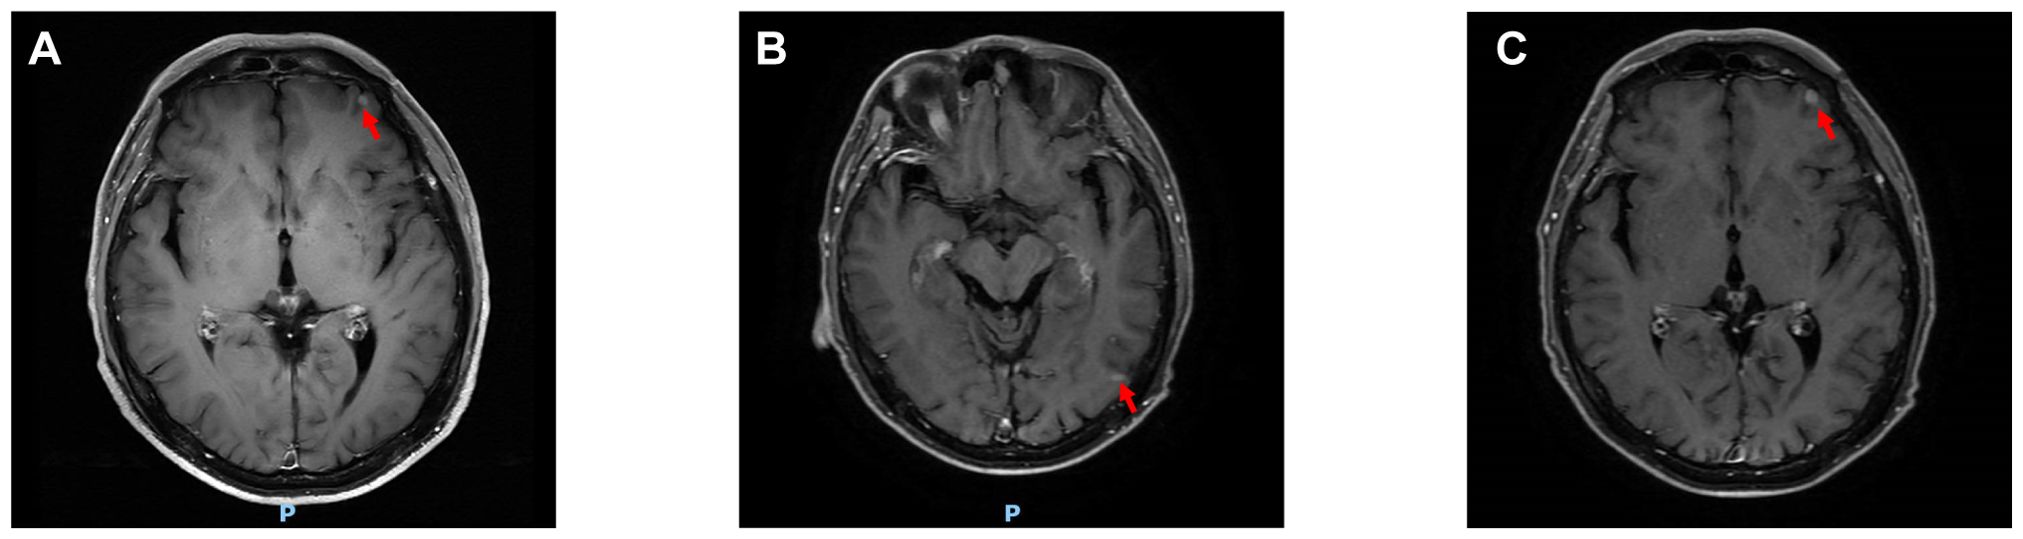

Male breast cancer is an extremely rare form of malignant tumor, and occult breast cancer is also an exceptionally uncommon disease. Given its rarity, diagnosing occult breast cancer in male patients presents significant challenges, and the diagnosis becomes even more difficult when the tumor exhibits characteristics of other neoplasms. For instance, this case report describes a male patient with occult breast cancer presenting with features typical of primary lung cancer. The uniqueness and complexity of this case lie in its clinical presentation: beyond typical axillary lymph node enlargement, the primary imaging feature was an isolated pulmonary mass lesion. This presented significant diagnostic hurdles. For the diagnosis of this case, we administered chemotherapy and intracranial radiotherapy to the patient. Therefore, sharing this rare case aims to heighten clinicians' awareness of differential diagnoses for metastatic cancer with an unknown primary site, particularly when pathological findings of pulmonary lesions do not align with conventional lung cancer markers.